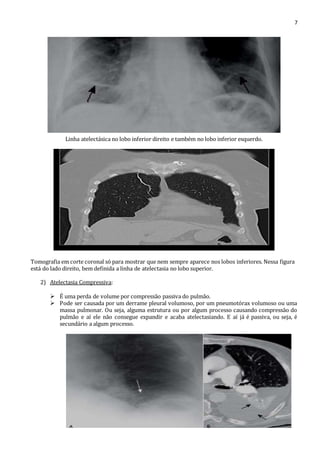

7

Linha atelectásica no lobo inferior direito e também no lobo inferior esquerdo.

Tomografia em corte coronal só para mostrar que nem sempre aparece nos lobos inferiores. Nessa figura

está do lado direito, bem definida a linha de atelectasia no lobo superior.

2) Atelectasia Compressiva:

 É uma perda de volume por compressão passiva do pulmão.

 Pode ser causada por um derrame pleural volumoso, por um pneumotórax volumoso ou uma

massa pulmonar. Ou seja, alguma estrutura ou por algum processo causando compressão do

pulmão e aí ele não consegue expandir e acaba atelectasiando. E aí já é passiva, ou seja, é

secundário a algum processo.

Aqui existe um derrame pleural. Tem a tomografia para comparar porque no Rx o derrame

não fica tão evidente. Mas existe um derrame pleural e uma atelectasia, um aumento da

densidade.